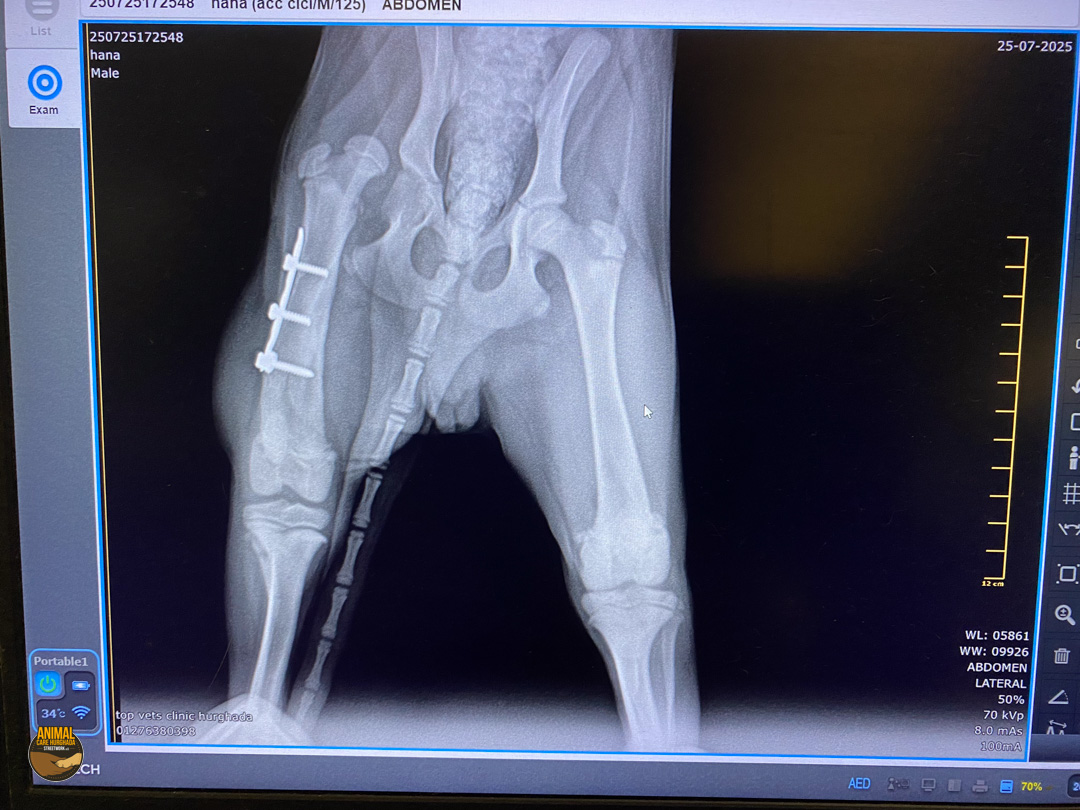

Pepe hat bereits einiges hinter sich – doch heute blickt er voller Zuversicht nach vorn. Eine aufmerksame Frau fand ihn verletzt auf der Straße, sammelte ihn liebevoll ein und brachte ihn in eine „Tierklinik“. Dort wurde Pepe operiert – leider jedoch nicht fachgerecht. Als er zu uns kam, wussten wir nicht genau, was bei ihm gemacht worden war. Also fuhren wir wenige Tage später mit ihm in die „Top Vet’s Clinic“ zur weiteren Untersuchung. Die Röntgenbilder brachten traurige Gewissheit: Pepe hatte sowohl eine gebrochene Hüfte als auch einen Bruch des Oberschenkelknochens – beides wurde in der ersten Klinik zwar operiert, allerdings leider sehr schlecht. Das Bein war steif, schmerzhaft und bereitete ihm große Probleme im Alltag. Schweren Herzens, aber in seinem besten Interesse, entschieden wir uns dazu, das Bein zu amputieren. Und siehe da – seitdem geht es Pepe endlich wieder gut!